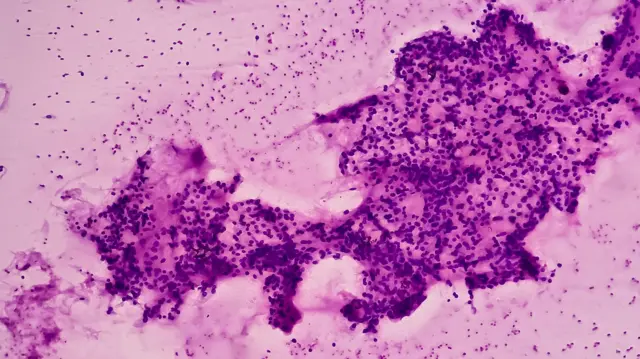

बीवी का कारण असामान्य योनि स्राव है. इससे मछली जैसी तीव्र गंध आती है. इसका रंग और गाढ़ापन अलग-अलग हो सकता है. यह भूरा और सफ़ेद भी हो सकता है.